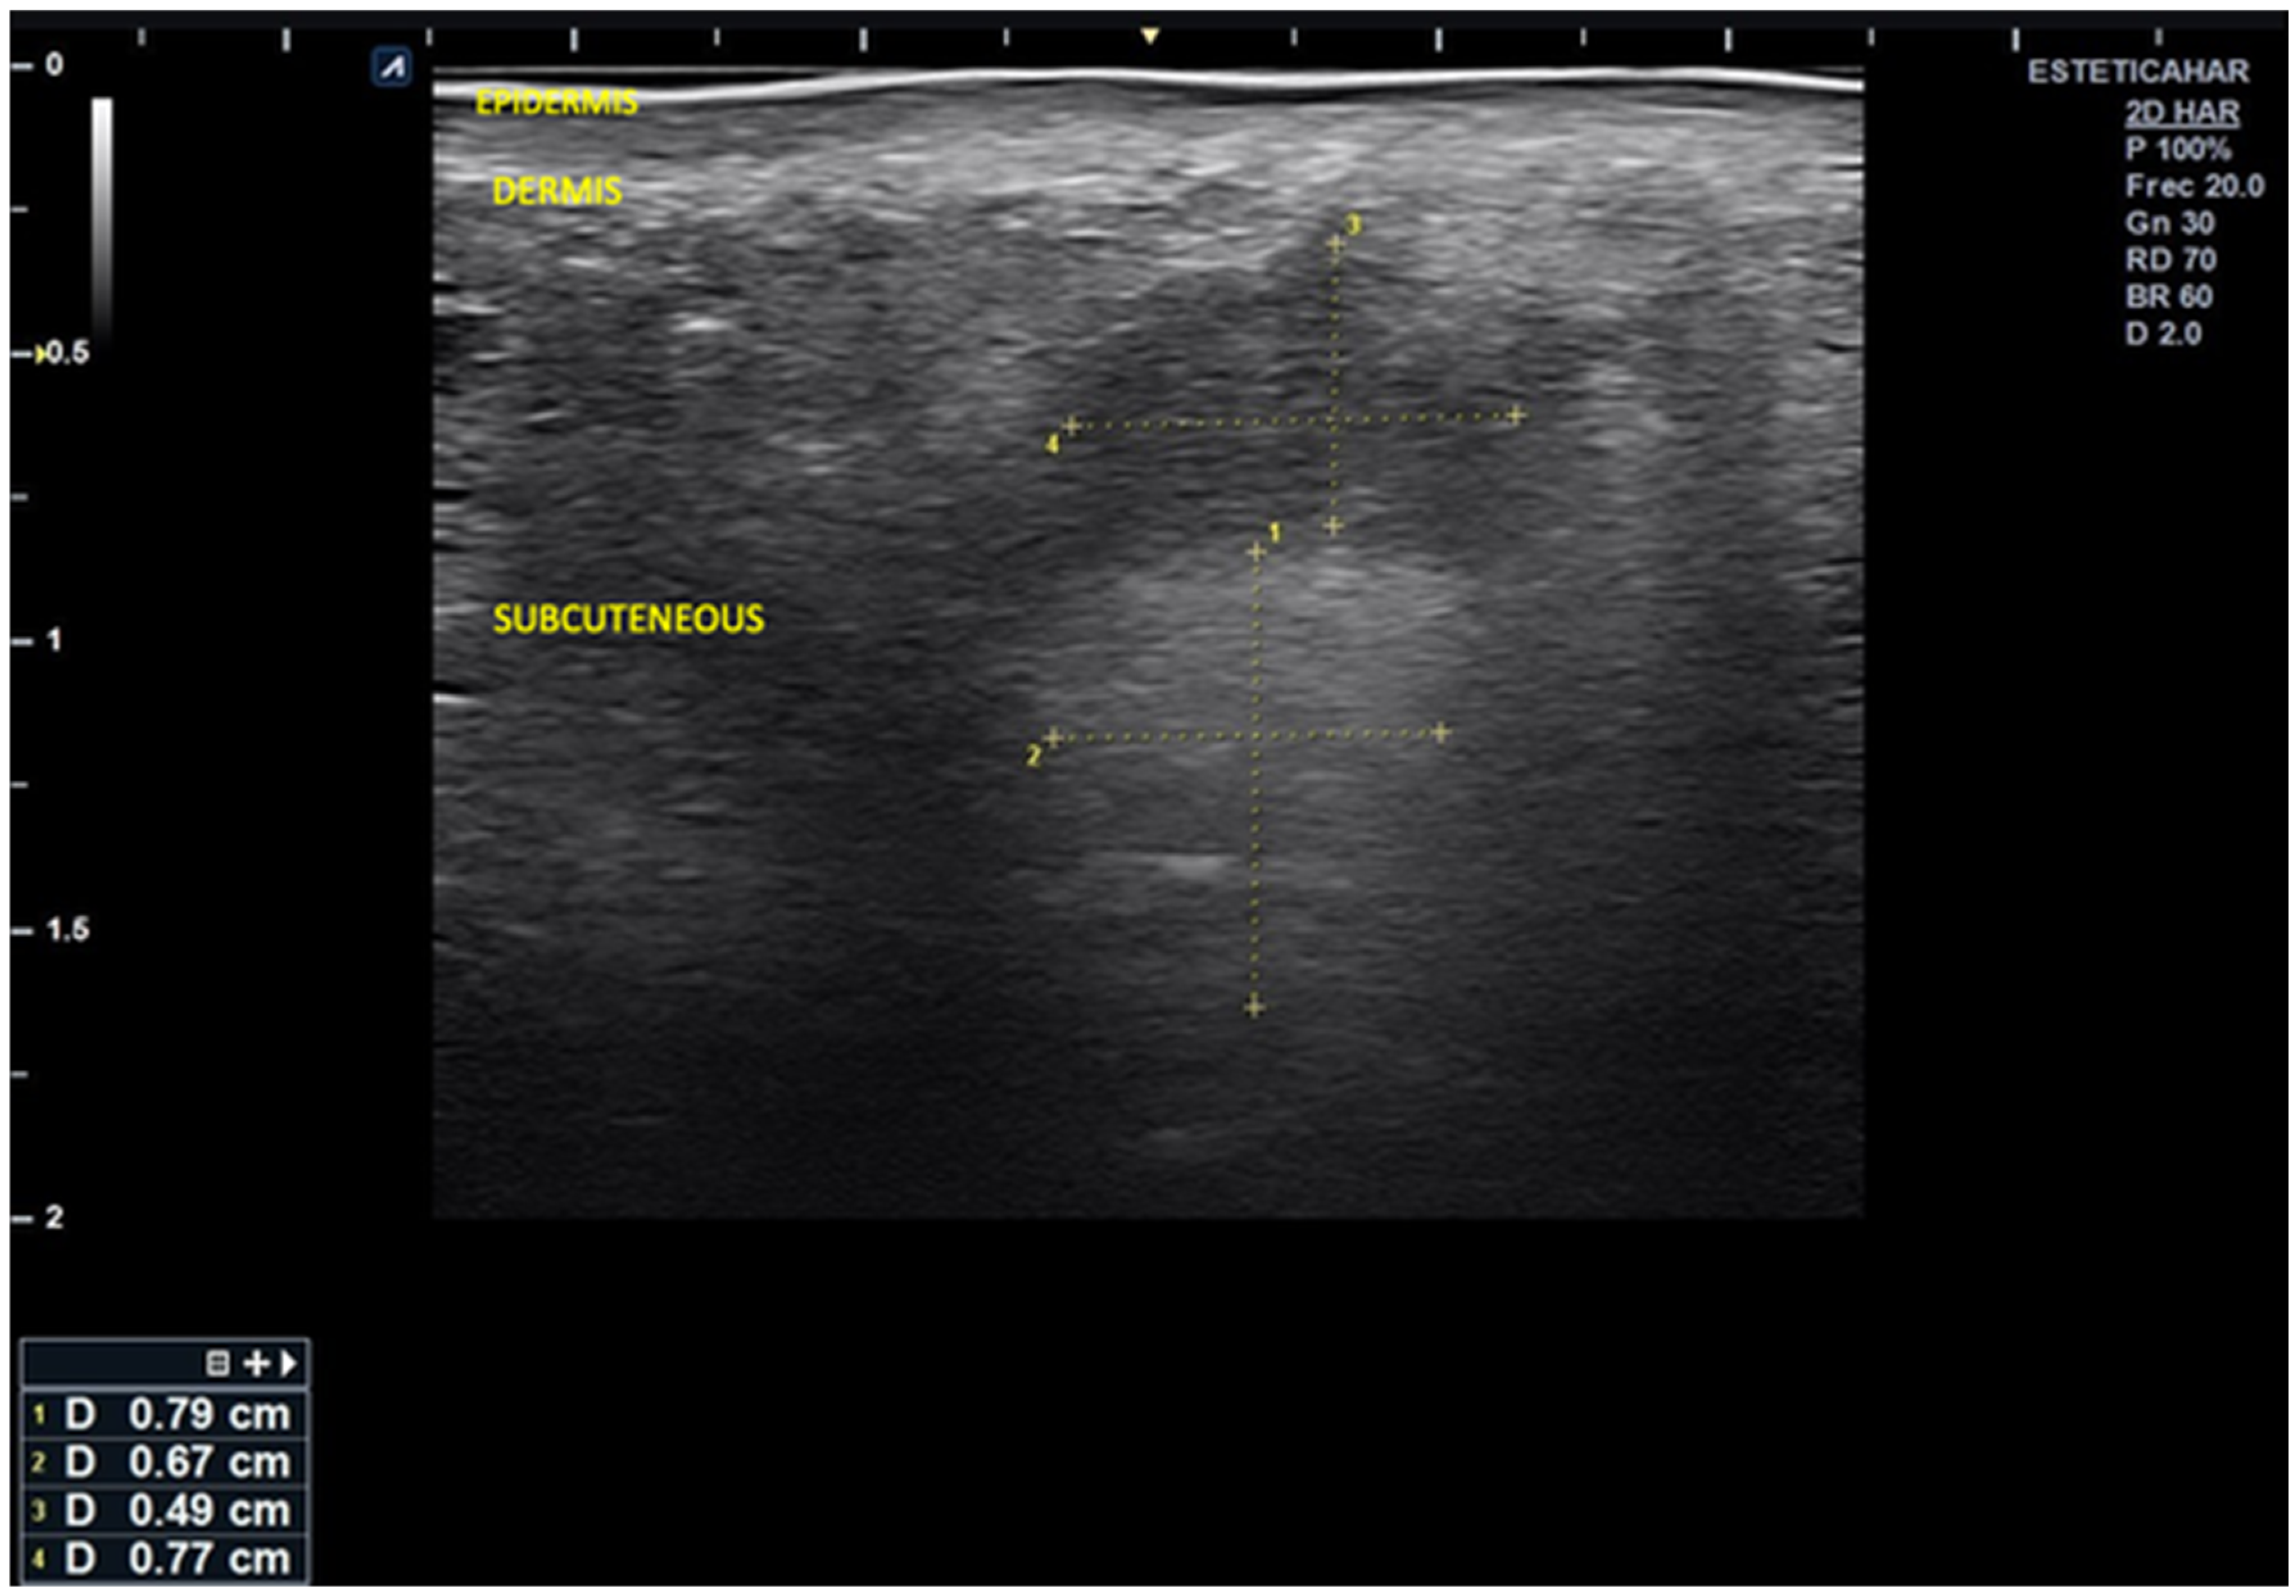

High-resolution cutaneous ultrasound demonstrated homogeneous hypoechoic images compatible with well-demarcated subcutaneous inflammatory infiltrates, with no evidence of fluid collections or necrosis.

Ultrasound imaging revealed alternating columnar hypoechoic areas and distributed linear hyperechoic zones. There were disruptions in the normal echoanatomy, as evidenced by diffuse hypoechogenicity starting at the basal dermis, which obscured the distinction of deeper anatomical planes and was associated with a slight increase in microvascularization.

In the right lateral submalar area, poor visualization of the soft tissue echoanatomy was noted, with uniform isoechogenicity extending from the posterior dermis to the bone interface. This finding is likely related to infiltration by dermal filler material that was poorly integrated into the surrounding tissue (Figure 2 and Figure 3).

Figure 3. Image of the center-right malar region showing disruption of the normal layered echoanatomy, with two well-defined, rounded areas. A superficial subcutaneous hypoechoic area measuring 0.49 × 0.77 cm is likely associated with the liquid component of the injected material. An underlying hyperechoic area measuring 0.79 × 0.67 cm is probably related to the solid portion of the hybrid filler.